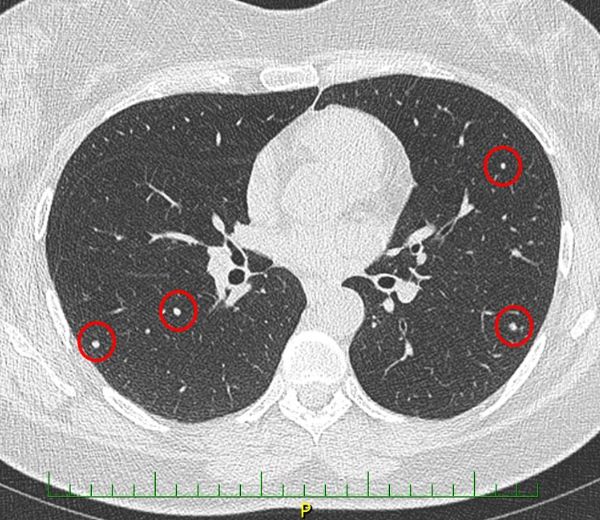

Do vaší ordinace vchází Milan Drahoš. Než se padesátiletý, velmi obézní muž dostane ode dveří k vámi nabízené židli, zadýchá se. Podle CT hrudníku, který si s sebou pacient přináší, má zvětšené uzliny v oblasti mediastina. Snímek odhaluje také mnohočetná ložiska plic. Není na co čekat, je třeba co nejrychleji zahájit léčbu. Ujmete se tohoto případu?